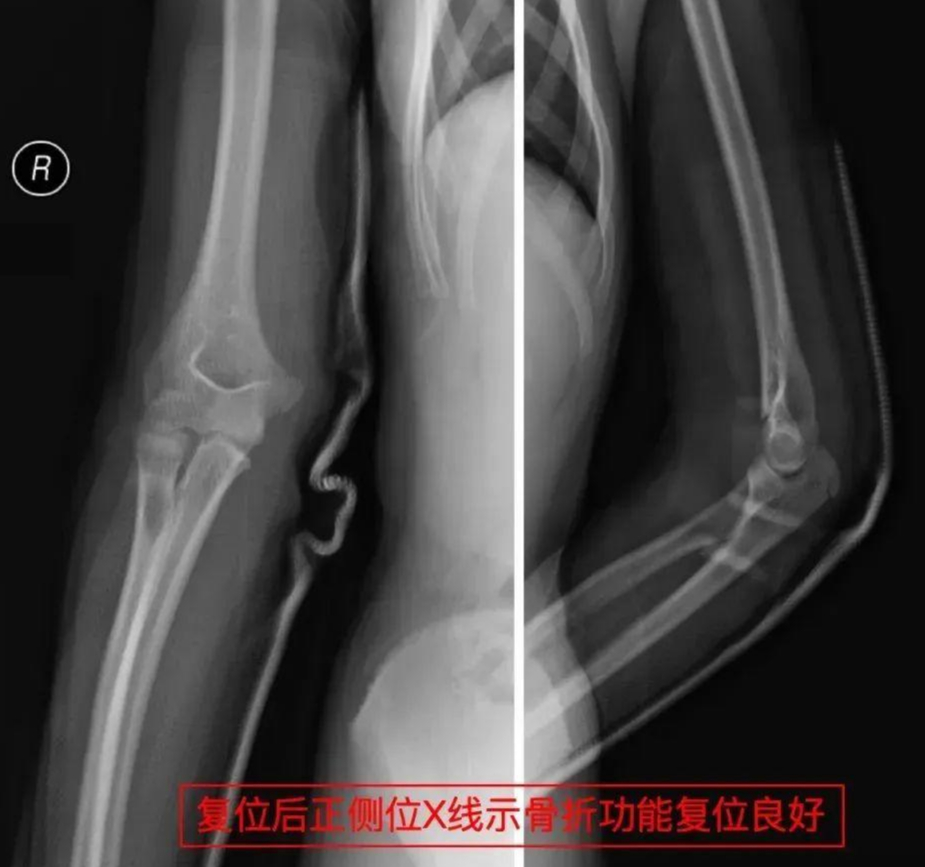

她赶紧带着孩子赶到医院,拍片、诊断、复位、固定,整个诊疗过程迅速又专业。主诊医生的精湛操作让孩子免于手术创伤,医护人员的人文关怀更令李女士动容。